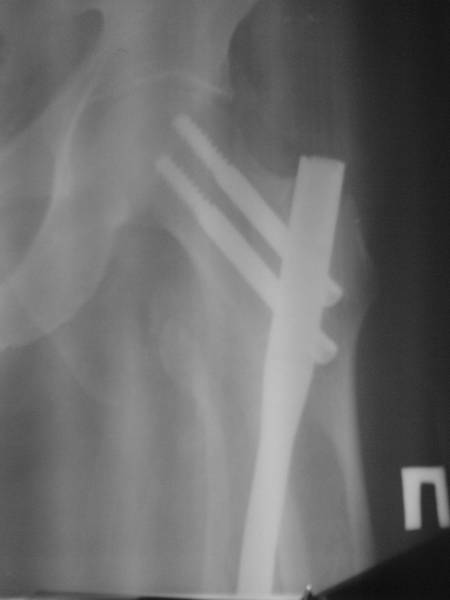

>> Если решили интрамедуллярным гвоздем, тогда во время или до операции

>> надо убедиться в отсутствии перелома латерального кортекса в

>> проксимальной части бедра.

>> Такие бывшие нестабильные переломы из-за отсутствия медиальной стенки

>> (малый вертел) имеют тенденцию уходит в варус.

>> Для предупреждения таких явлений необходимо провести превентивный

>> шуруп-стопор в передне-заднем направлении латеральнее гвоздя.

>    Латеральная стенка здесь явно отсуствует ( ушла с м вертелом)

>    Точку ввода гвоздя желательно медиализировать, можно до ямки, несмотря

> на латерализованную версию импланта, а отклоняющий винт провести  в зоне

> дуги Адамса, и возможно второй витн после введения 2-х шеечных винтов

между

> ними для предупреждения миграции. Недостаток данного гвоздя надличие

только

> размров 9-10 мм, что тоже мешает бороться с варусом проксимального

отломка.

Нашел в архиве наш проблемный остесинтез  на таком-же штифте с  варусным

смещением проксимального отломка, который ,правда, успешно

консолидировался в срок.